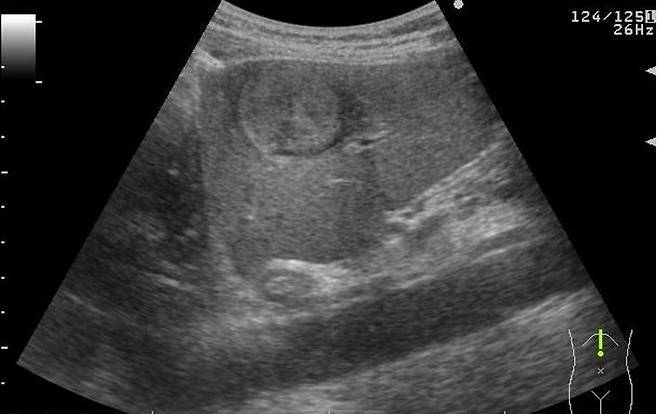

초음파 검사를 통해 지방간 유무 확인